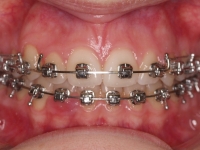

La paciente O.O. acude a nuestra consulta por:

– Canino 13 e incisivo lateral 42 en posición ectópica.

– Canino 23 incluido.

Con lo que decide realizarse un tratamiento de ortodoncia de duración de 24 meses con brackets damon Q.

CASO COMPLETO: